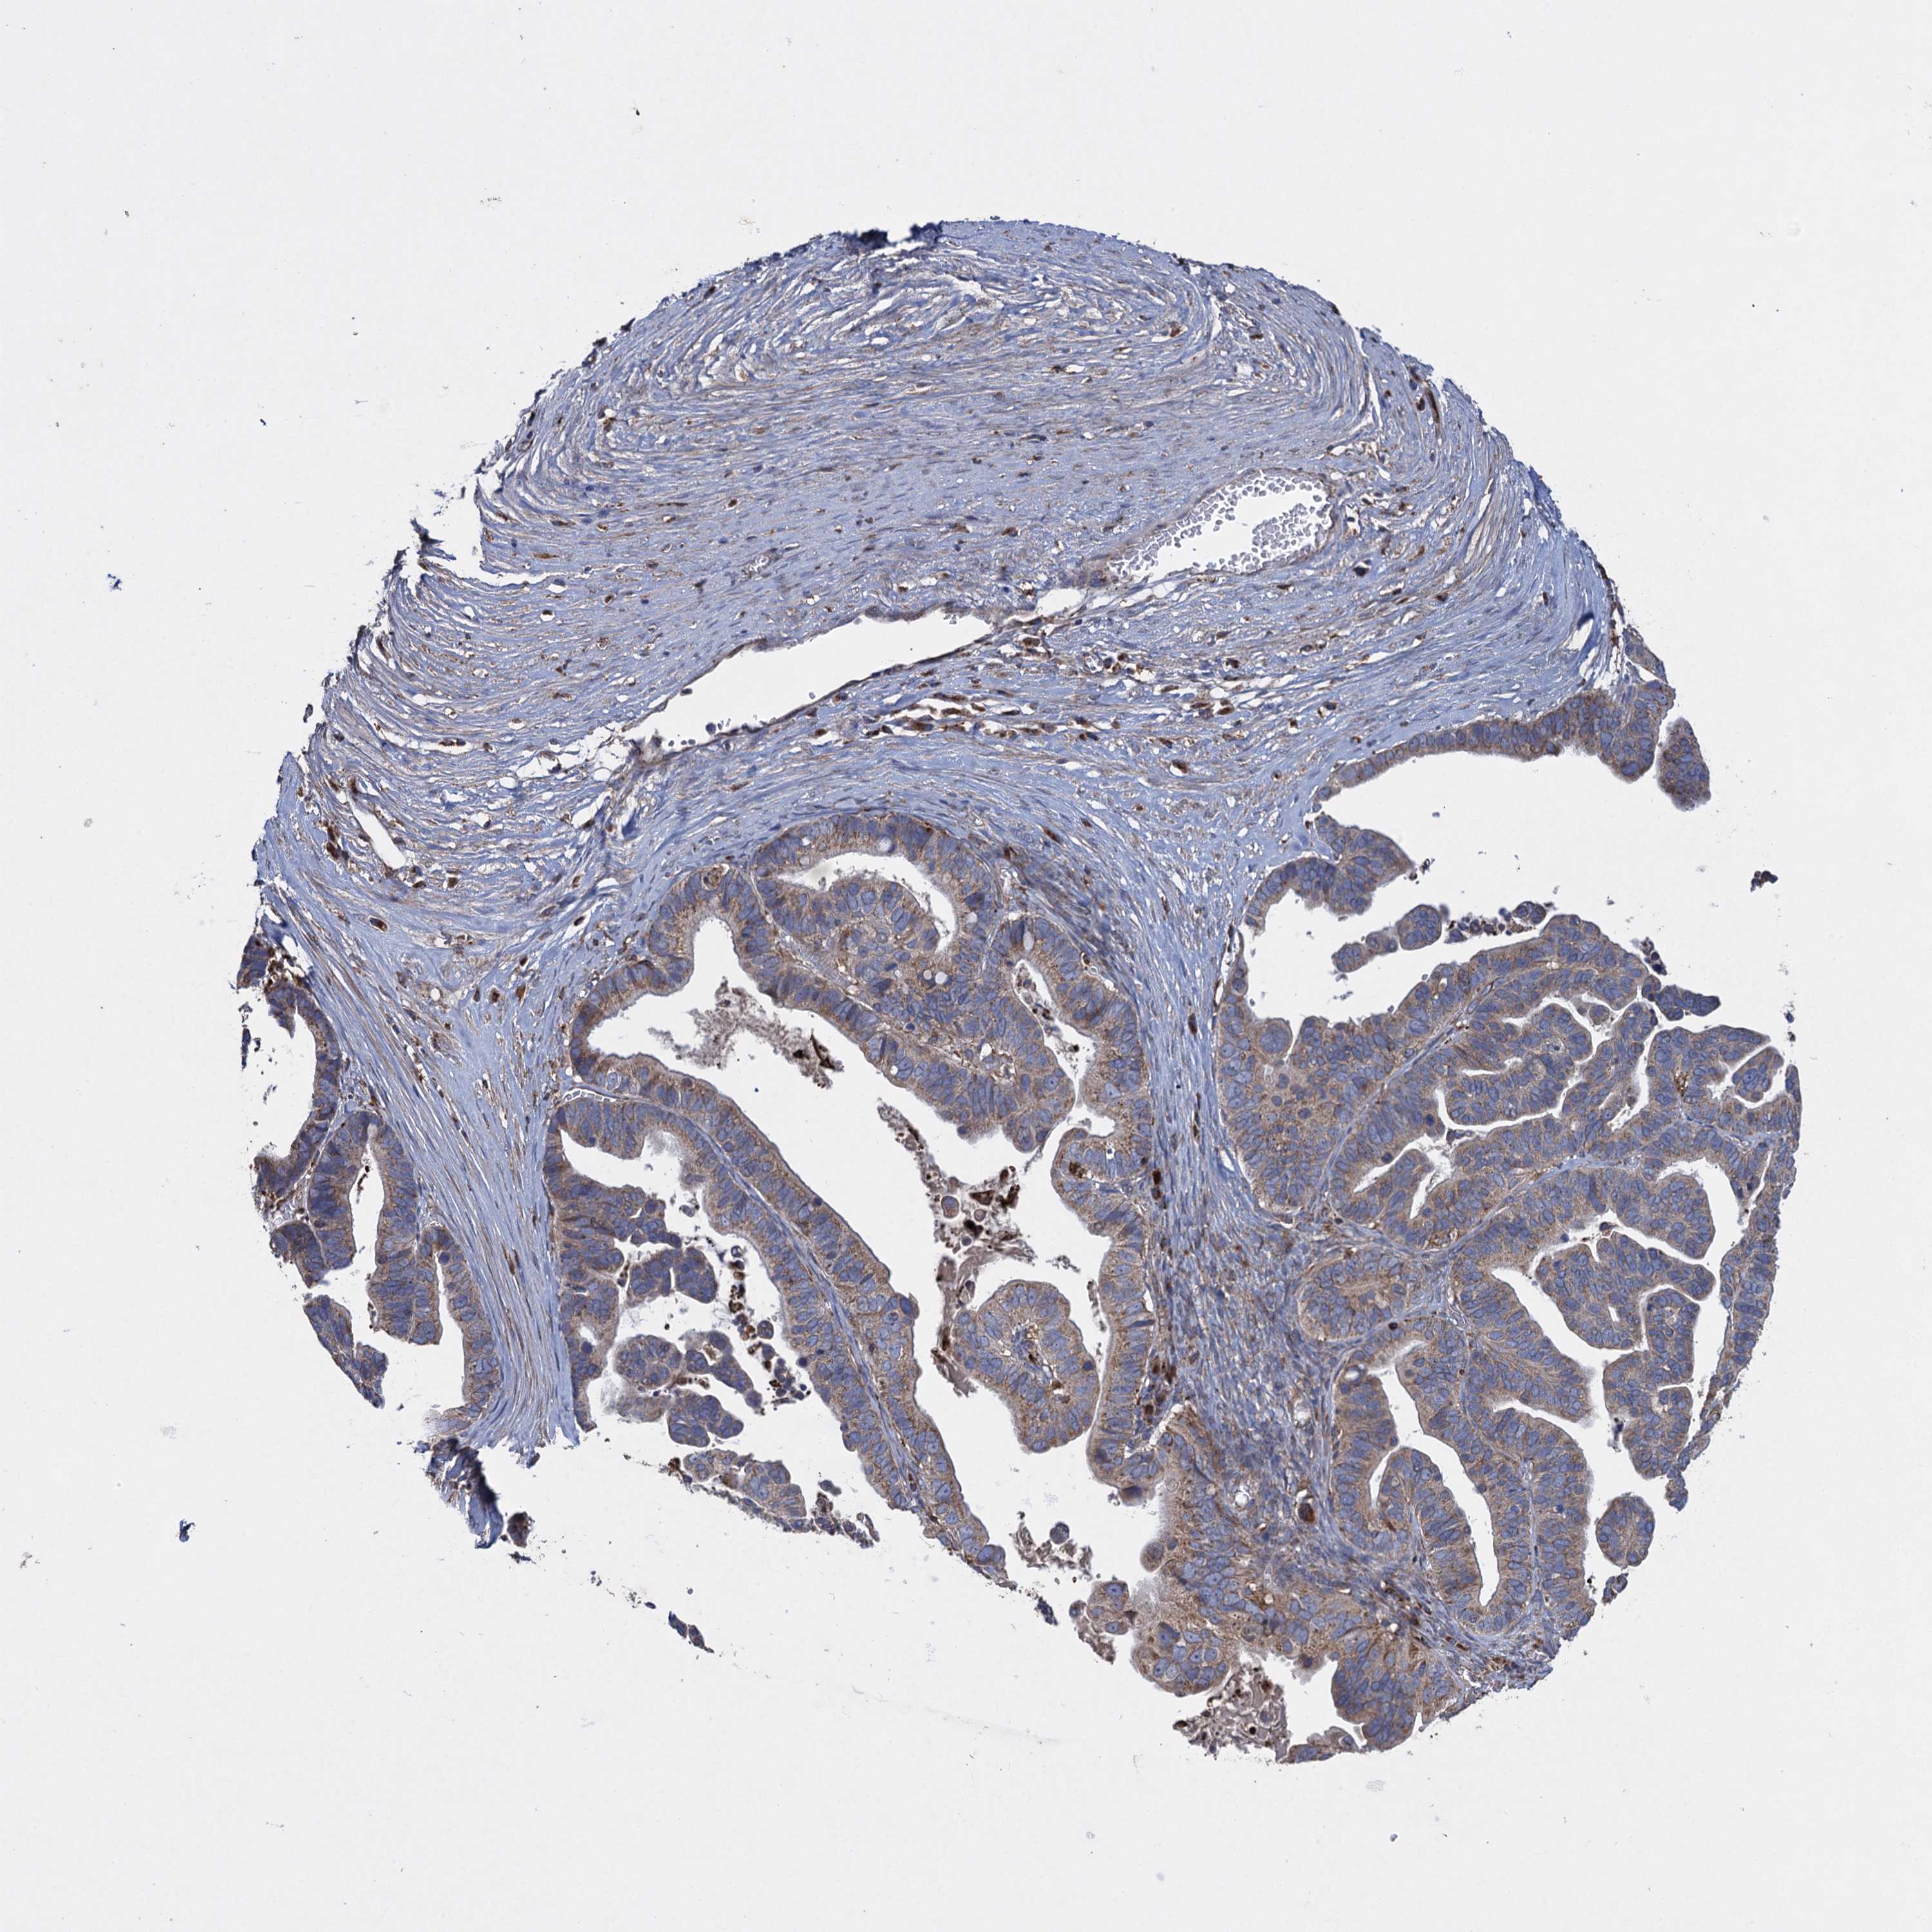

OVARIAN CANCER - Protein expressioni

A mouse-over function shows sample information and annotation data. Click on an image to view it in a full screen mode. Samples can be filtered based on level of antibody staining by selecting one or several of the following categories: high, medium, low and not detected. The assay and annotation is described here.

Note that samples used for immunohistochemistry by the Human Protein Atlas do not correspond to samples in the TCGA dataset.

Antibody stainingi

Antibody staining in the annotated cell types in the current human tissue is reported as not detected, low, medium, or high, based on conventional immunohistochemistry profiling in selected tissues. This score is based on the combination of the staining intensity and fraction of stained cells.

Each image is clickable and will lead to virtual microscopy that enables deeper exploration of all samples and also displays staining intensity scores, fraction scores and subcellular localization as well as patient and tissue information for each sample.

Antibody HPA041174

Antibody HPA041390

Cystadenocarcinoma, serous, NOS

Carcinoma, endometroid

Cystadenocarcinoma, mucinous, NOS

Carcinoma, NOS